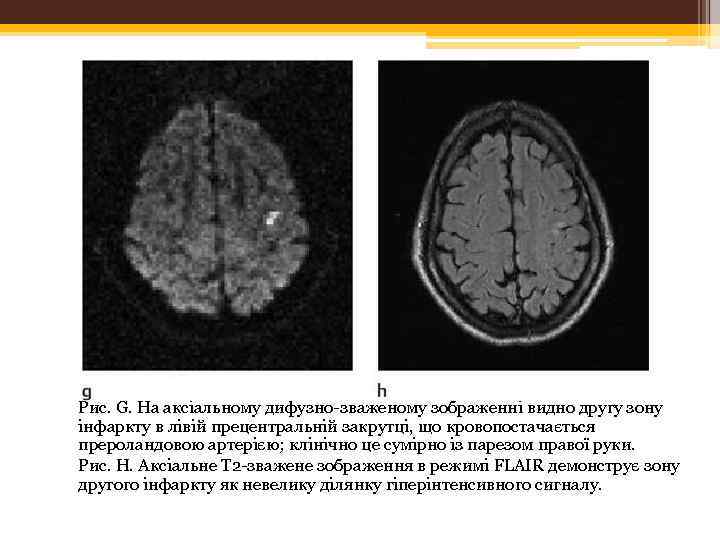

Рис. G. На аксіальному дифузно-зваженому зображенні видно другу зону інфаркту в лівій прецентральній закрутці, що кровопостачається прероландовою артерією; клінічно це сумірно із парезом правої руки. Рис. Н. Аксіальне Т 2 -зважене зображення в режимі FLAIR демонструє зону другого інфаркту як невелику ділянку гіперінтенсивного сигналу.